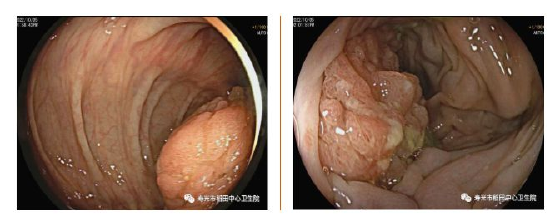

1、胃镜病例

下图为一升结肠早癌病例,病人在潍坊市人民医院行腹腔镜手术治疗,病理报告为绒毛管状腺瘤,部分高级别上皮内瘤变。